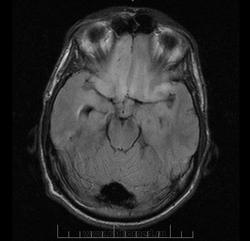

Пациент 28 лет. Жалобы на головную боль в течении 1 месяца.

Изменение поведения.

Уважаемые коллеги, помогите, пожалуйста, разобраться. ОбЪемный процесс обеих лобных долей,распространяющийся на передние отделы мозолистого тела (более вероятно глиального ряда)? Неоднородное контрастное усиление от двух узловых образований  в правой лобной доле и зона контрастного усиления в передних отделах мозолистого тела, или есть "слабое" накопление контраста и слева? Ликворная киста переднего рога левого бокового желудочка или это кистозный компонент опухоли, и как расценить очаги повышенного МР-сигнала по Т2ВИ и Tirm паравентрикулярно треугольнику правого бокового желудочка (как отек?). Ниже представлены томограммы с контрастным усилением (ранее на первой группе снимков были представлены отсроченные тмг)

Что то мне подсказывает на Гадовист Вы поскупились, очень слабое контрастирование(% содержания Gd очень низок, сорее всего 0,25) , пока мысль только на метастатическое поражение передних отделов мозолистого тела и правой лобной доли с выраженным цитотоксическим отеком. А что по поводу консультации онколога?

Контраст Омнискан, как обычно 10,0мл, пациент никуда не обращался, терпел месяц с нарастающими головными болями. Думаю, что опухоль глиально ряда распространяется через мозолистое тело на оба полушария, откуда  изначально исходит трудно сказать, эти "загадочные" глиальные опухоли по разному копят контраст , а то и вообще не накапливают. А что по поводу кисты?Может быть это супраселлярная арахноидальная киста, которая распространяется в передний рог левого бокового желудочка? И что за очаговые паравентрикулярные зоны в области треугольника правого бокового желудочка  с жидкостными сигнальными характеристиками (отек?) Спасибо, что ответили.

Глиоматоз похоже. Киста может быть деформированной кистой прозрачной перегородки. Мало аксиалов.